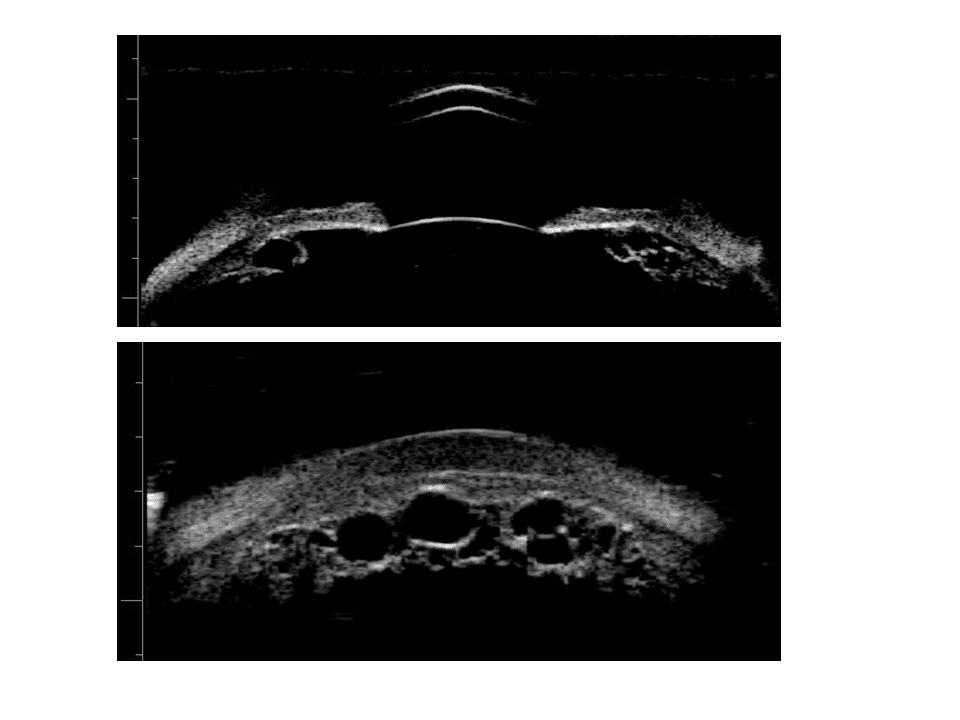

Le syndrome d’iris plateau est caractérisé par une fermeture aigue ou chronique de l’angle irido-cornéen secondaire à des anomalies de forme et de position du corps ciliaire et de la racine de l’iris. Un corps ciliaire anormalement volumineux et positionné de façon très antérieure va mécaniquement rapprocher la périphérie de l’iris du trabéculum. A l’occasion d’une dilatation pupillaire, ou même parfois spontanément, la racine de l’iris va s’épaissir et former l’équivalent d’un bourrelet qui va combler le récessus angulaire très étroit et venir s’apposer au trabéculum. En cas de syndrome d’iris plateau pur, ce seul mécanisme va aboutir à la fermeture de l’angle irido-cornéen sans participation d’un mécanisme de blocage pupillaire. De ce fait, l’iridotomie ou l’iridectomie ne modifieront pas la position de l’iris en ne permettront pas une réouverture de l’angle irido-cornéen. Il est à noter que, dans de rares cas, de multiples kystes du corps ciliaire ou de l’épithélium pigmenté de l’iris peuvent aboutir à un tableau clinique très comparable. L’examen ultrabiomicroscopique permet dans ces cas d’éliminer ces diagnostics différentiels et d’orienter vers une prise en charge thérapeutique adaptée.

Figure 2. Diagnostic différentiel : polykystose ciliaire.